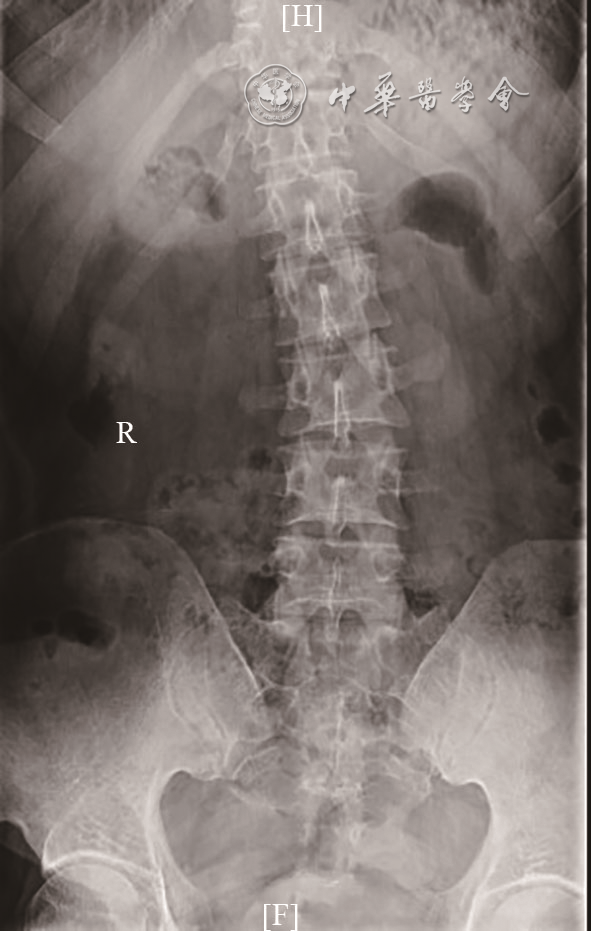

图1 难治性脊柱侧弯患者胸腰椎正位片(2019-01-06)。胸椎向右侧弯曲,腰椎向左侧弯曲